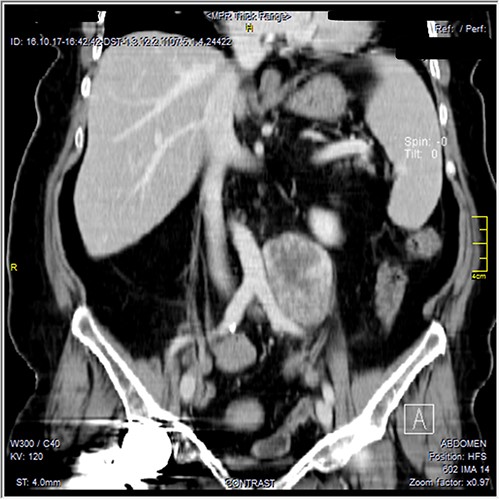

The CT scan was confirming the presence of a relatively well-defined retroperitoneal lobulated mass lesion seen extending along the left lateral wall of the distal abdominal aorta and left common iliac artery and anteromedial to the left psoas muscle. It showed heterogeneous intense peripheral enhancement during the porto-venous phase, the fat planes were preserved between the lesion and adjacent structures with no gross evidence of local invasion (Figs 1–3). The first diagnostic possibility was made as a retroperitoneal paraganglioma based on the CT appearance. The surgical decision of tumor removal was done.

Contrast-enhanced reformatted coronal images—soft tissue window, show well-defined peripherally enhancing mass lesion seen along the left lateral wall of distal aorta and left common iliac artery. Preserved fat planes between the lesion and adjacent aorta and common iliac can be well appreciated with no signs of local invasion. A metal artifact from right hip prostheses is noted.